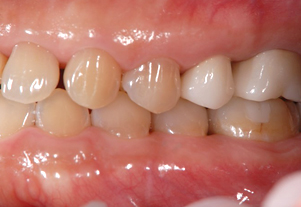

症例3(再生療法)

Before

After

- POINT

- 他院で歯周病の治療をしていましたが、なかなか歯周病が改善されず、セカンドオピニオンにて来院された患者様です。歯周病の進行した部分に再生療法を行い(エムドゲインを使った歯茎の手術)ホームケアを徹底することで改善されました。

今後も継続したメインテナンスが必要です。